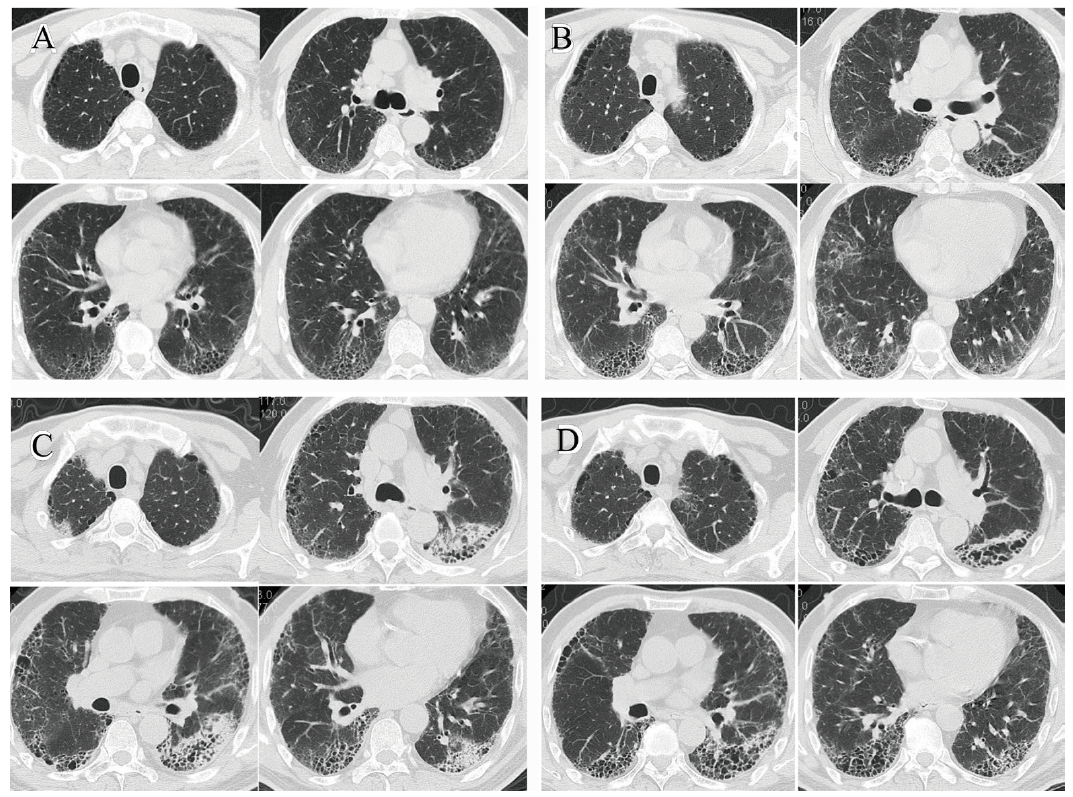

复习患者起病以来影像学检查结果:2012年9月胸部CT示肺气肿合并双下肺少量间质样改变(图1A);2014年9月胸部CT示间质样改变增多,双下肺网状影逐渐转化为蜂窝样改变(图1B);2018年2月胸部CT显示间质样改变继续增多,双下肺蜂窝样改变(图1C)。2018年2月26日患者住院肺功能检查示:轻度限制性通气功能障碍,肺弥散功能中度下降,肺总量、残气量减少,残总比正常。患者莱切斯特咳嗽问卷评分总分17.77分(生理评分4.63分,心理评分6.14分,社会评分7分)。根据患者的长期咳嗽、咳痰症状、影像学改变及肺功能结果诊断:CPFE;IPF。

图1 患者胸部影像学变化

注:A为2012年9月胸部CT,示肺气肿合并双下肺少量间质样改变;B为2014年9月胸部CT,示间质样改变增多,双下肺网状影逐渐转化为蜂窝样改变;C为2018年2月胸部CT,示间质样改变继续增多,双下肺蜂窝样改变;D为2018年12月胸部CT,间质样炎症范围变小。

2018年2月26日开始逐渐加量并长期应用吡非尼酮0.4 g每日3次,联合NAC 0.6 g每日3次抗纤维化治疗。2018年2月28日患者症状好转出院。出院时患者有少量胃肠不适,用短期护胃治疗后好转。随访至2018年12月,患者莱切斯特咳嗽问卷评分改善情况为1.05分(生理评分改善0.62分,心理评分改善0.43分)。患者肺功能(表1)、胸部CT明显改善(图1D),肺部间质样炎症范围变小。